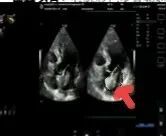

術后超聲

術后病理顯示,患者左房腫瘤為良性黏液瘤,完整切除后無需后續(xù)治療。經過10天的康復治療,老人順利出院。這一案例中,多學科團隊通過術前風險分層、術中精密協(xié)作、術后個體化護理,為高齡復雜心臟疾病患者的救治積累了臨床經驗